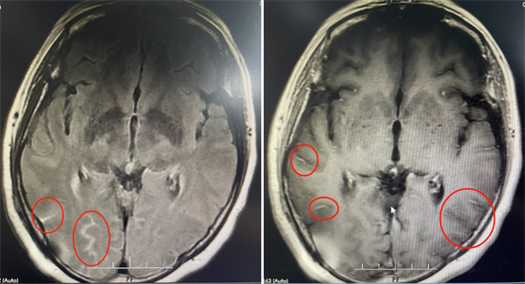

该院神经内一科副主任匡祖颖接诊后,通过腰穿检查,在患者的脑脊液涂片中发现了隐球菌,从而确诊为隐球菌脑膜炎。

影像资料

尽管立即采用了抗真菌等对因治疗,但患者在住院期间还是出现了左眼视力下降,连光感都丧失了。复查腰椎穿刺发现脑脊液压力增高,提示颅高压。为避免长期高颅压导致头痛及颅神经损伤,匡祖颖安排患者转入神经外科行脑室腹腔分流术。